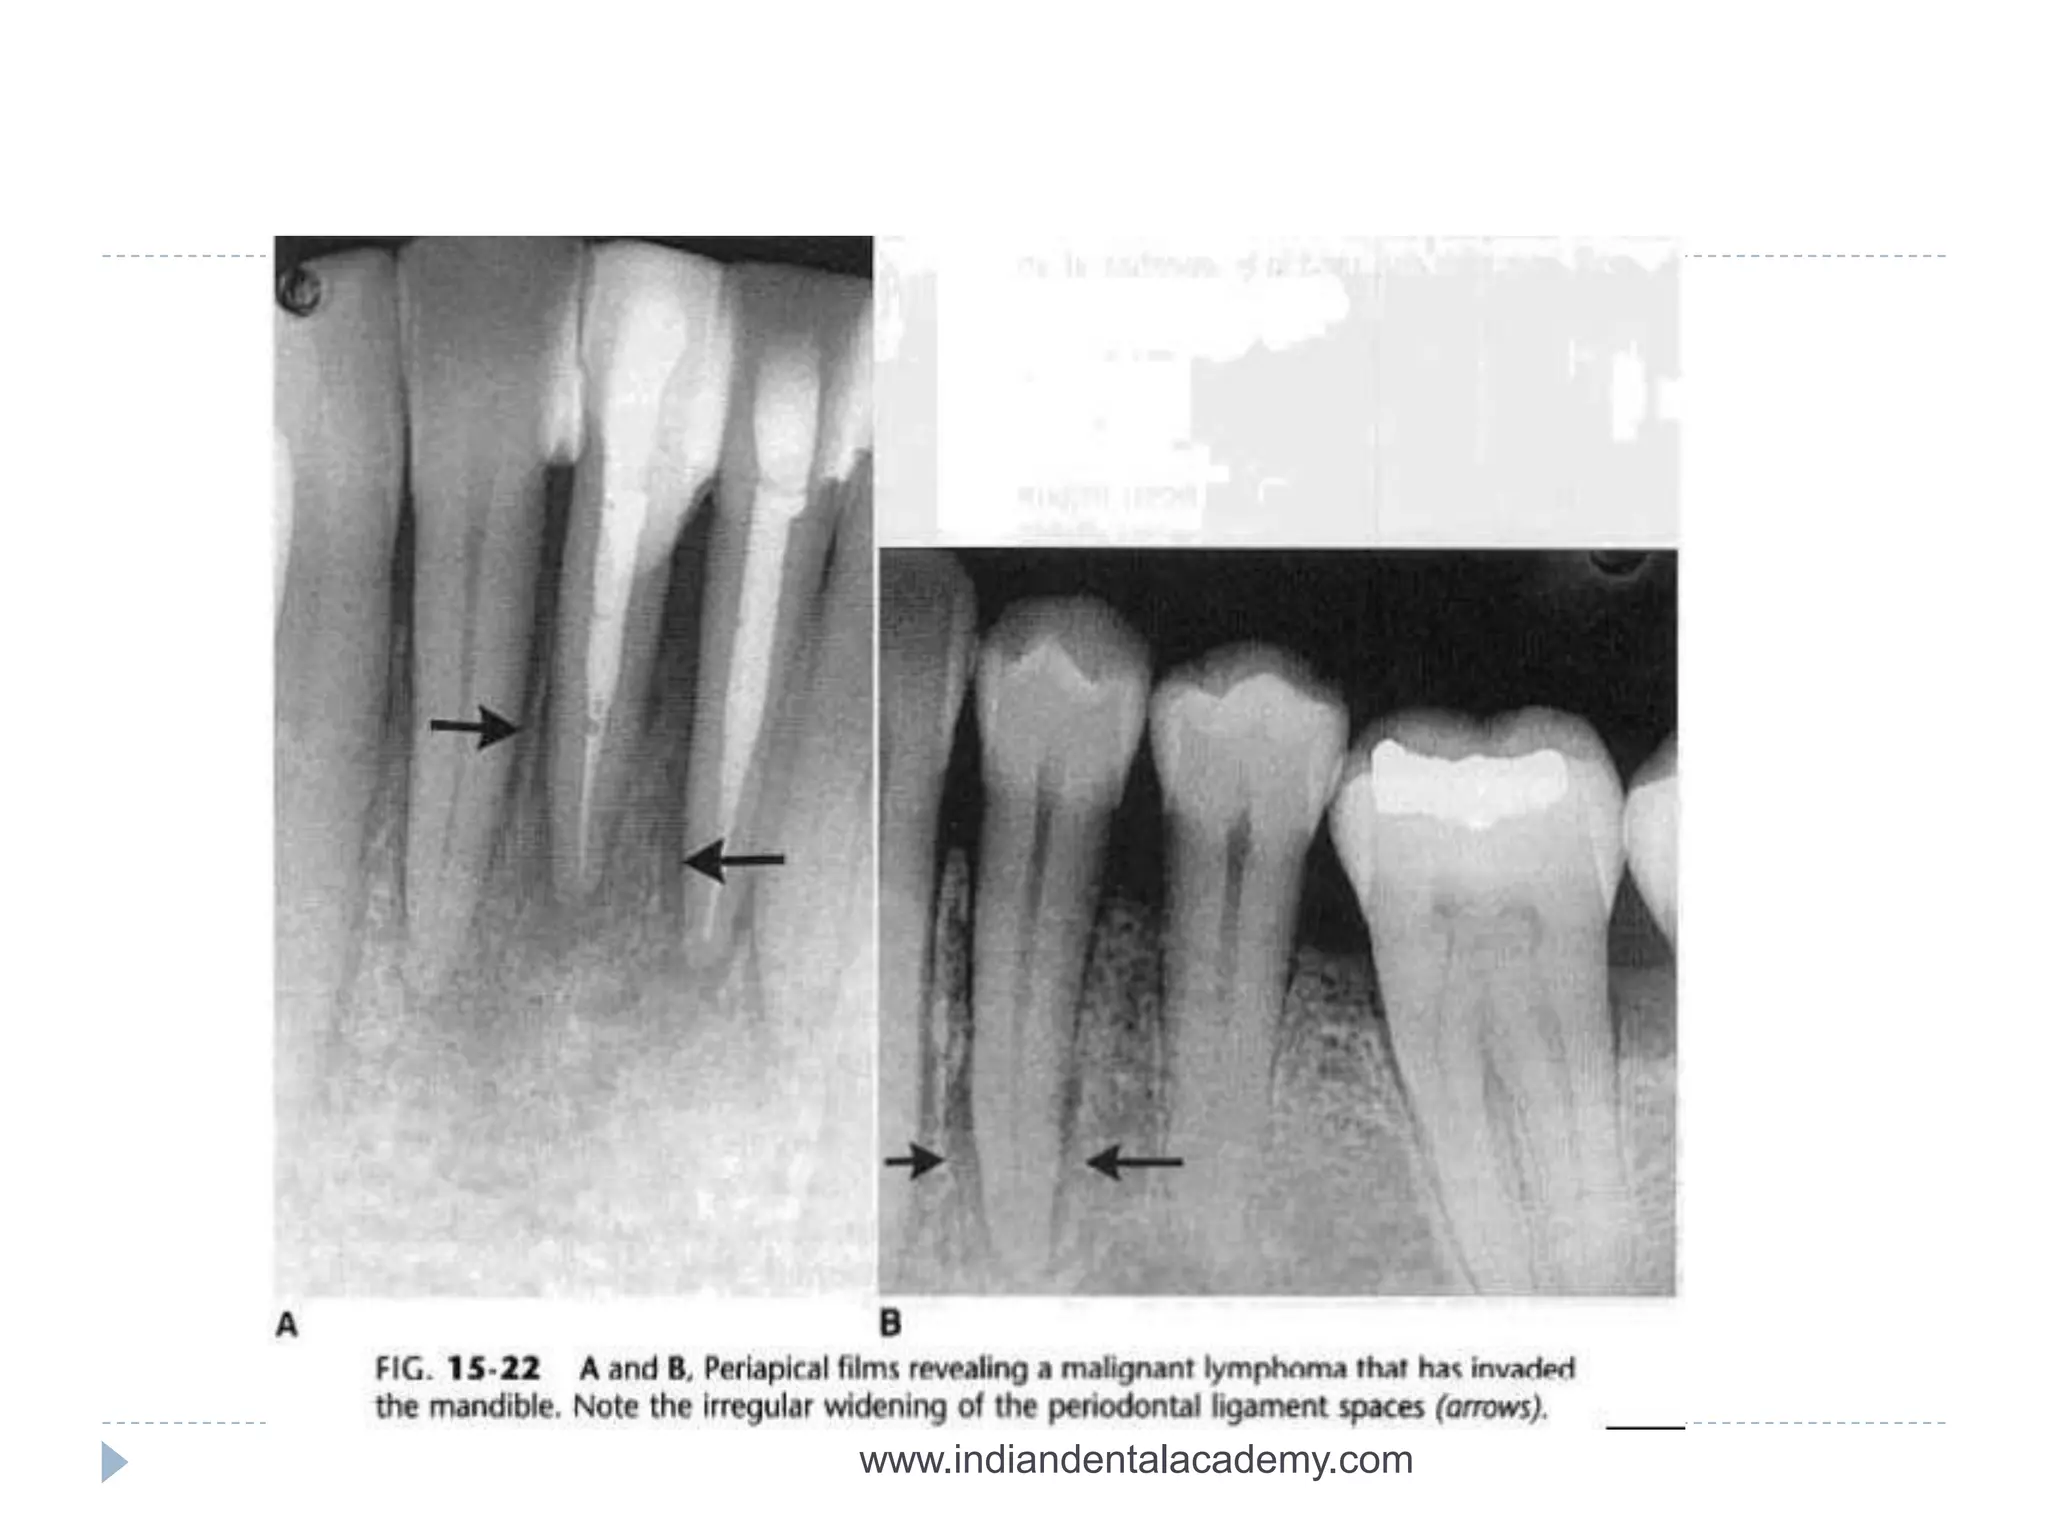

A and B periapical films reveals malignant lymphoma invading

mandible.,irregular widening of pdl space is seen.

A and Bperiapical films reveals malignant lymphoma invading mandible.,irregular widening of pdl space is seen. www.indiandentalacademy.com